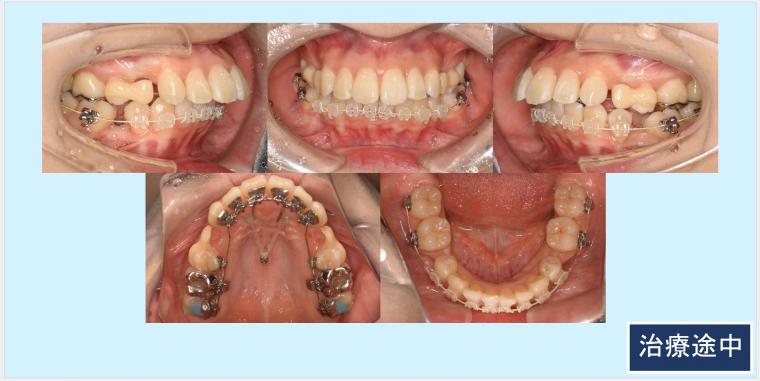

上顎両側4番、下顎両側5番を抜歯して、上下顎前歯部を後方移動致しました。

上顎臼歯部の頬側に歯科矯正用アンカースクリューを埋入して臼歯部の固定を行い、上顎前歯部を後方移動させていきました。また、ガミースマイルの改善のために上顎口蓋正中にも歯科矯正用アンカースクリューを植立させて、上顎前歯部に圧下力を加えました。

最終的な微調整では正中を出来る限り一致させる為に、顎間ゴムを使用して頂きました。

◎ハーフリンガル:上顎 カスタムメイド型リンガルブラケット矯正装置(インコグニート)下顎 セラミックラビアルブラケット矯正装置